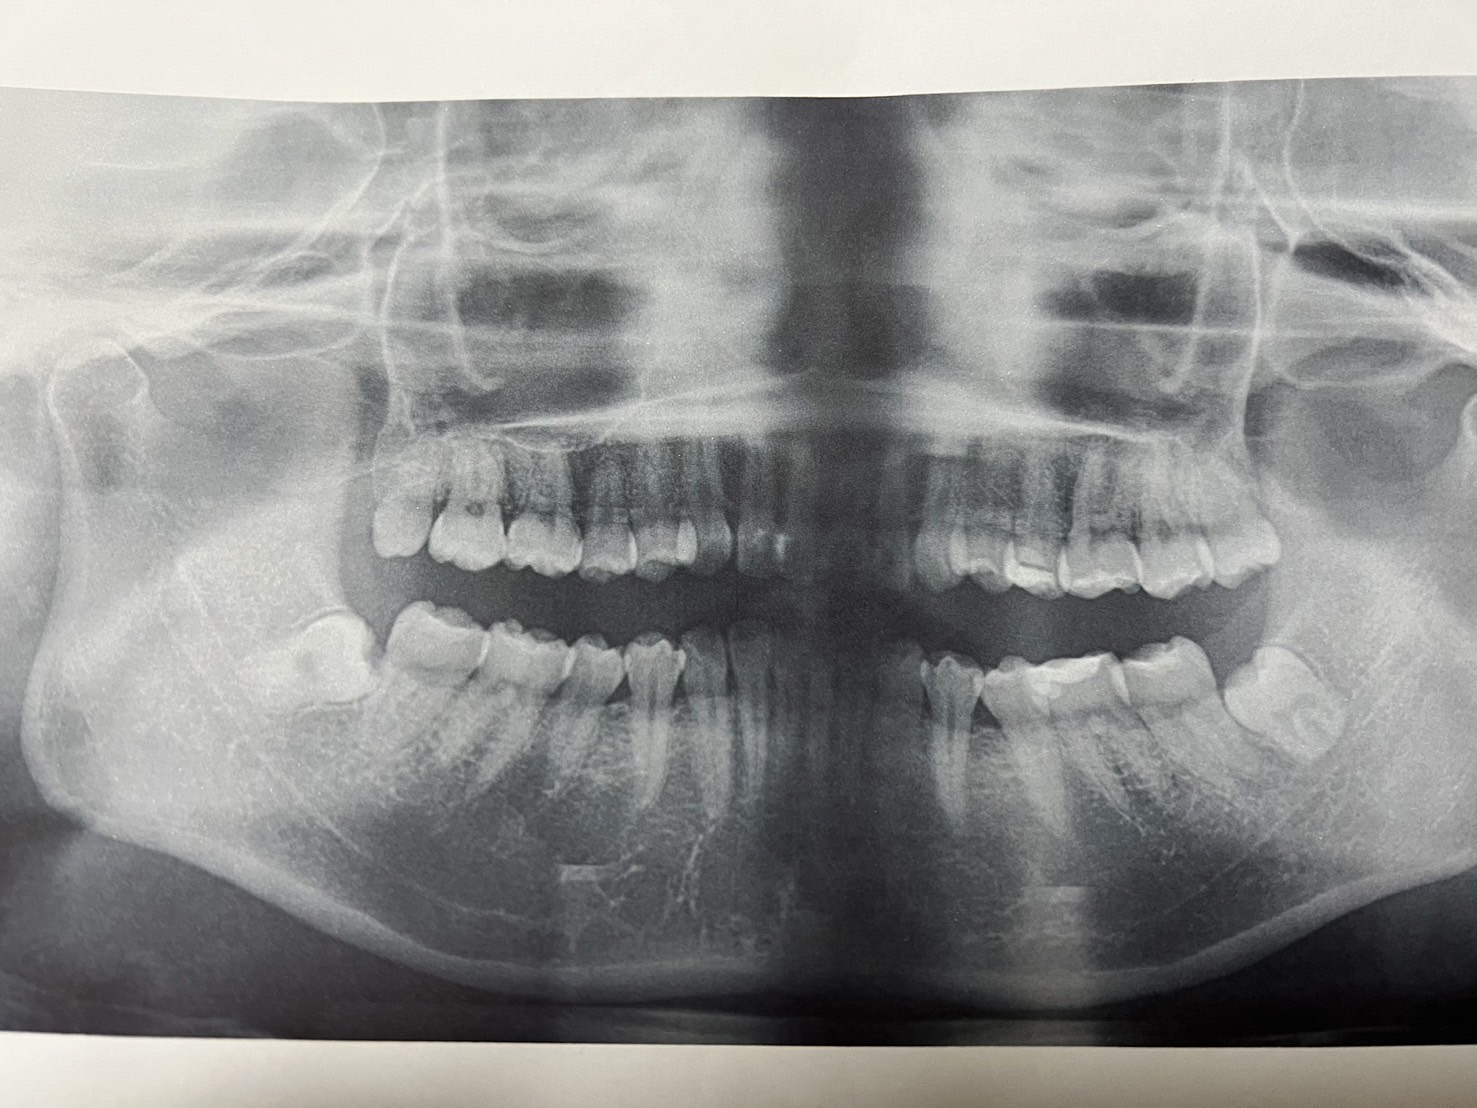

これは前からのレントゲンです。

下の歯の親知らずが暴れてみんな窮屈そう‥

私の寝相と同じなんですよ親知らずが😒

で、よく見たら歯の根っこが踊ってるみたいで可愛い🤡

ちなみにですが、読者の方であのレントゲン見て異常な箇所があれば教えてください!!

なんでも、気になったとこがあれば(笑)